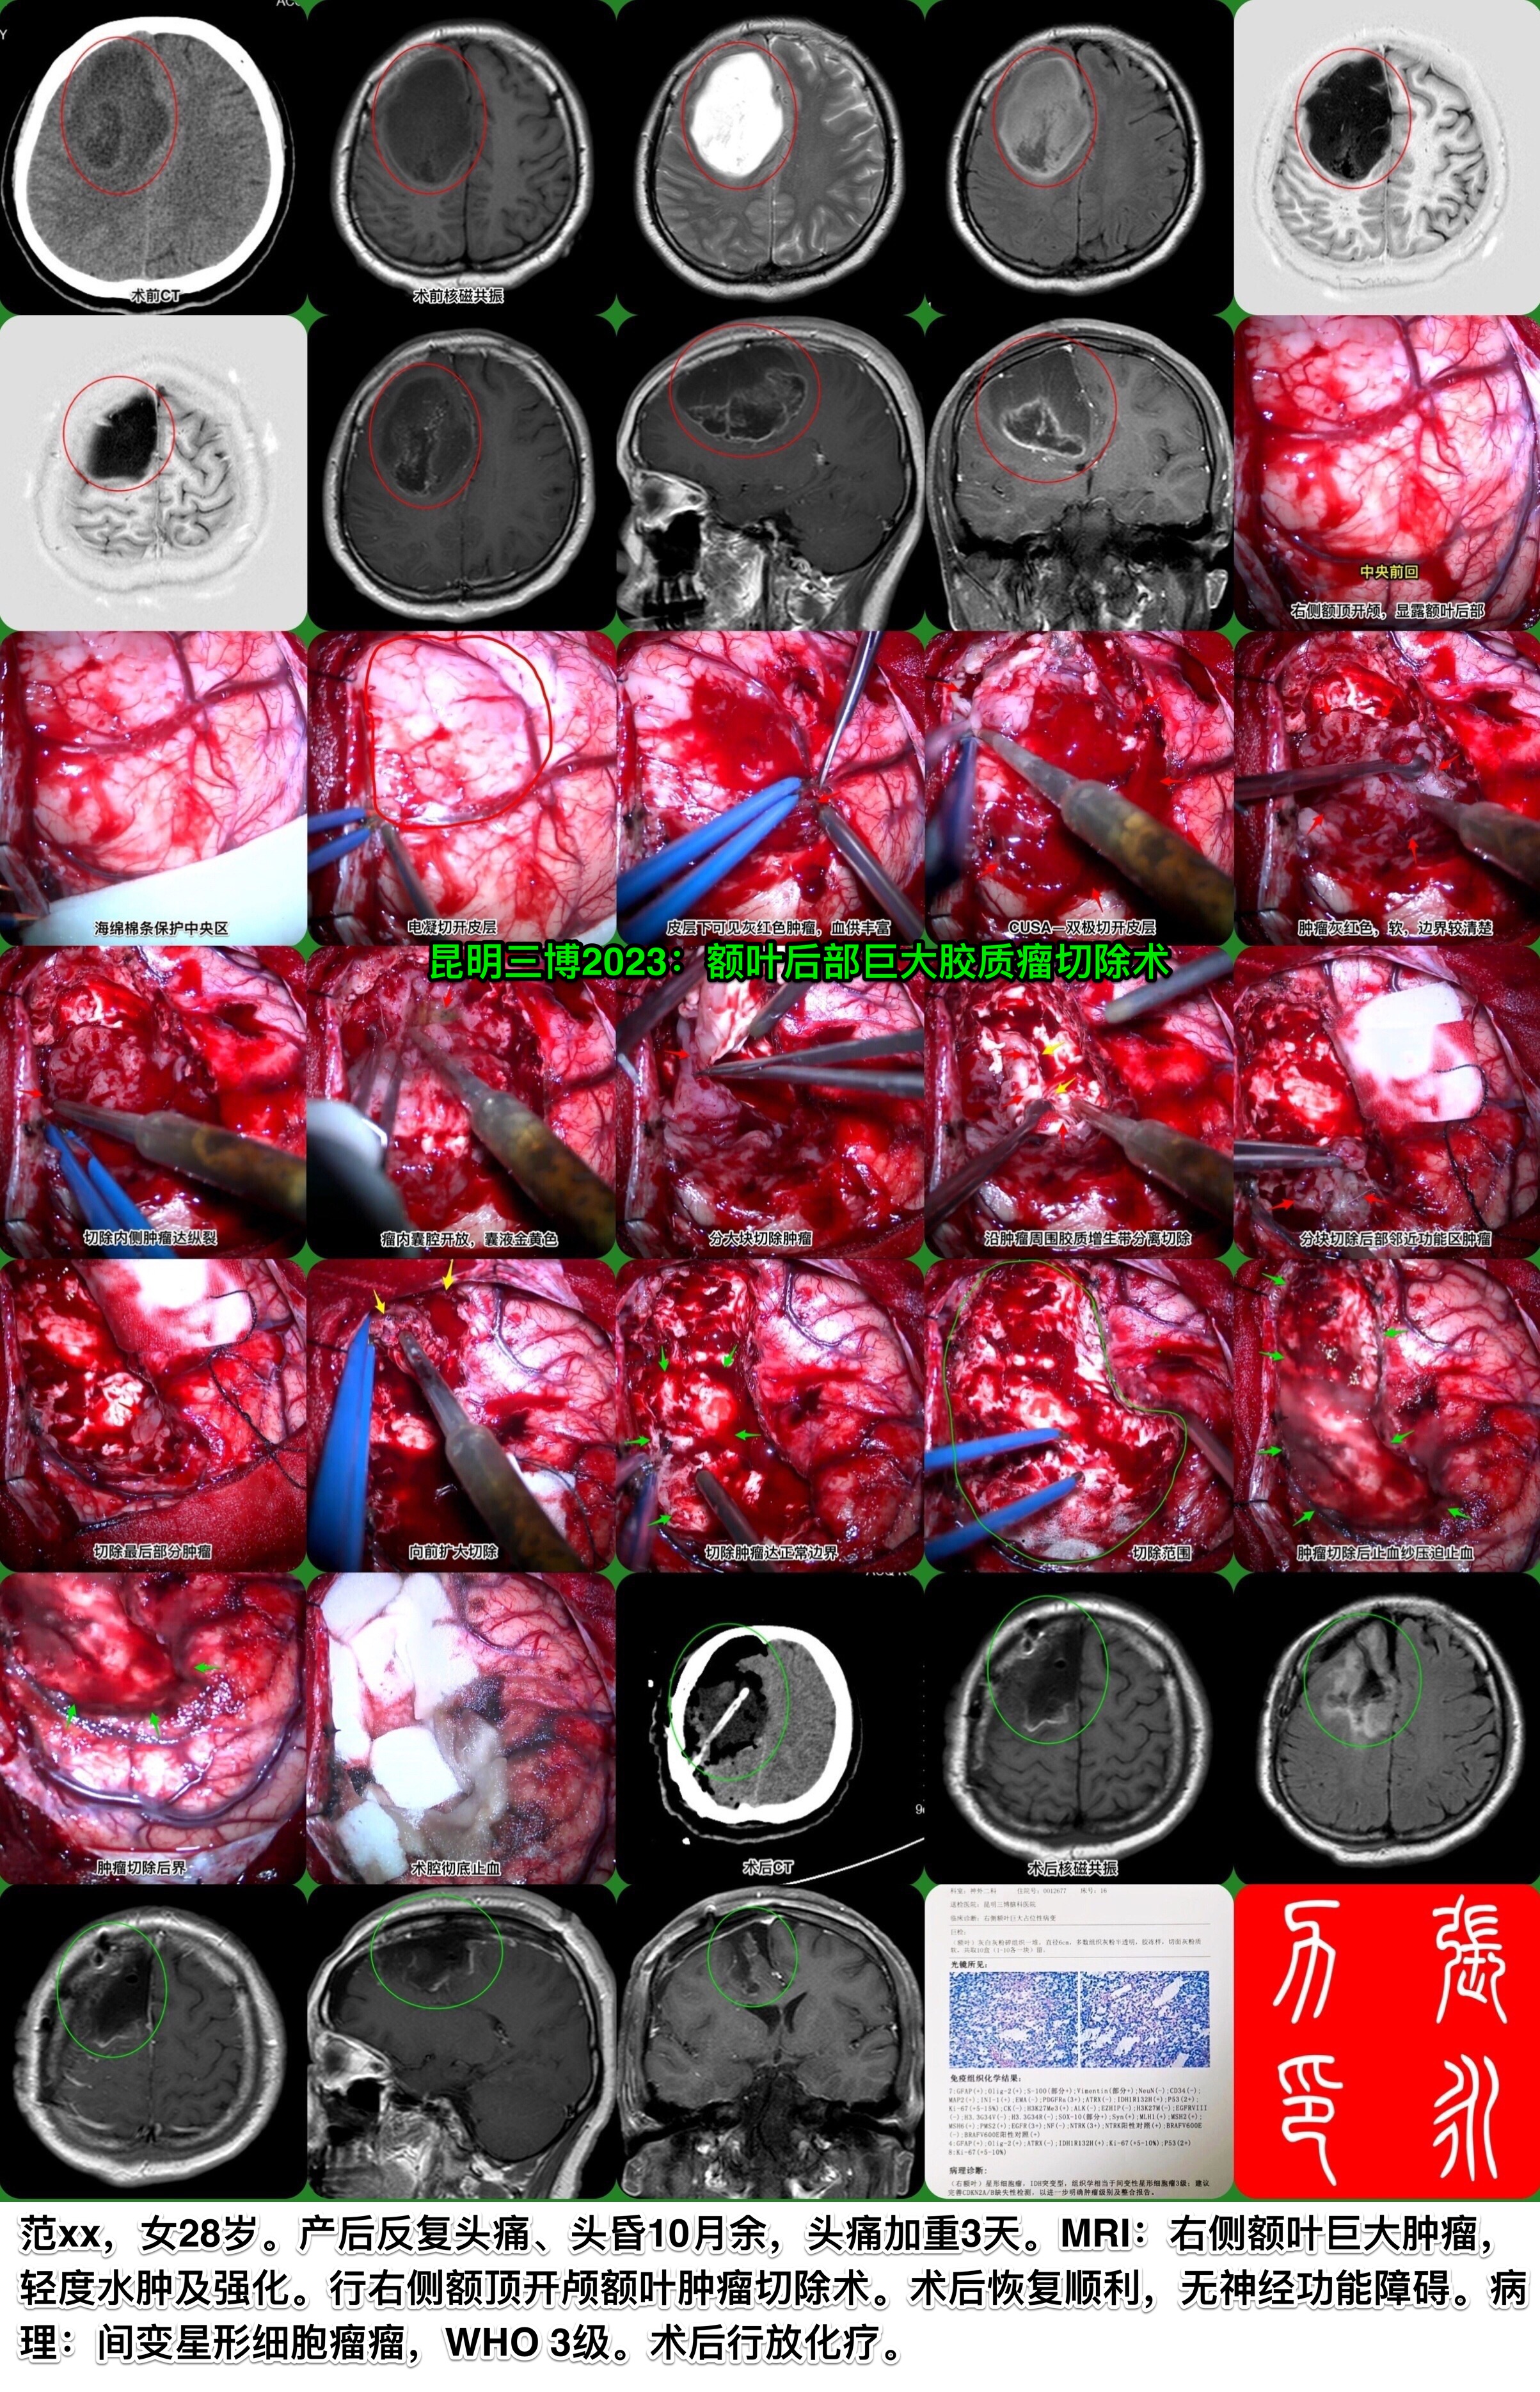

昆明三博2023:额叶后部巨大胶质瘤切除术

张永力

昆明三博脑科医院